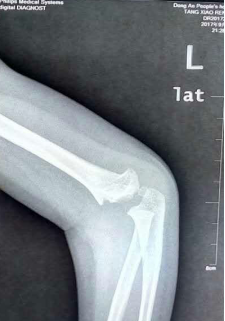

手术前X片:提示患儿尺桡骨干双骨折,尺桡骨断端有成角、短缩及移位

手术后X片:提示患儿尺桡骨骨折解剖复位,弹性髓内钉置入准确到位